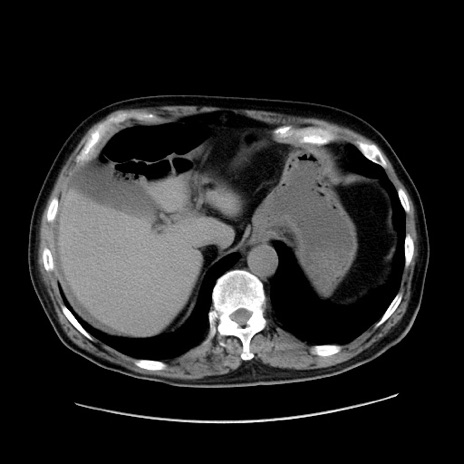

冠状断像

【症例】80歳代男性

【主訴】臍周囲痛

【現病歴】約6時間前から臍下部痛が出現。次第に腹部膨隆・背部痛も生じてきたため来院。背部痛の場所は変化しない。

【身体所見】意識清明、BT 36.3℃、BP  131/87mmHg、P 87bpm、SpO2 100%(RA)、臍周囲自発痛・圧痛あり、反跳痛なし、自発痛部位に一致して板状硬あり、腹部膨隆、腸雑音減弱、CVA tenderness両側陰性。

【データ】WBC 19600、CRP 0.33